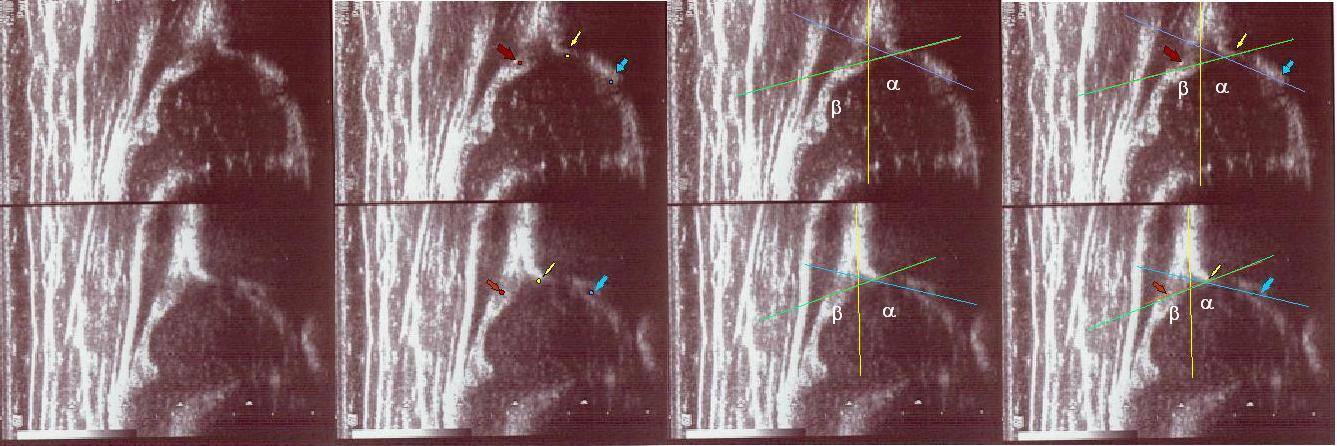

Type IIa+(GN coming to maturity) 6 weeks (below)

the bony roof satisfactory modeling

the bony rim angular but bony roof is only satisfactory ,the first part of bony roof is very good,but the second tail (deeper) is only satisfactory.

the cartilage roof cover the head;

the arrows show labrum (red) ;

the bony rim (yellow);

the lower iliac margin (blue) ,

the bony roof line (blue) is extends tangential to the lower iliac margin and tangent to the bony rim

the cartilage roof line(green) is drown tangential to the bony rim and through the middle point of the labrum echo;

asymmetry in the loose joint capsule; family DDH( when it occurs ask always about it)

the baseline (yellow) is drown parallel to ilium echo through the point of the junction of the perichondrium,the periosseum and ilium.

type I (abow) 6 weeks the bony roof is good

the bony rim blunt

the cartilage roof line(green) is drown tangential to the bony rim and through the middle point of the labrum echo ;

asymmetry in the loose joint capsule ,family DDH( when it occurs ask always about it)

type IIa ( below ) 4 weeks the bony roof is adequate

the bony rim rounded

the bony roof line (green) is extends tangential to the lower iliac margin and tangent to the bony rim

the cartilage roof(blue) is drown tangential to the bony rim and through the middle point of the labrum